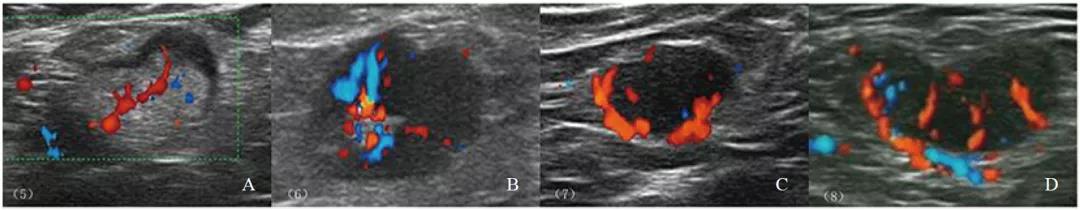

彩色多普勒超声检查发现,非转移性淋巴结多表现为淋巴门型血流(94.62%)。中央型、周围型和混合型血流在转移性淋巴结组百分比为7.69%、2.88%、49.04%,明显高于非转移性淋巴结组0.77%、0.77%及3.85%(P<0.01)。74.04%转移性淋巴结血流丰富,而非转移性淋巴结仅17.69%血流丰富,两组之间差异有统计学意义(P<0.001)。使用血流丰富程度诊断腋窝淋巴结灵敏度、特异度、AUC分别为74.0%、82.3%、0.782。RI≥0.7时特异度最高(98.4%),但灵敏度低(26.0%),AUC为0.622。开始增强时间诊断转移性淋巴结差异无统计学意义(P>0.05)。CEUS检查中,转移性淋巴结多表现为非均匀性增强(P<0.001,图2~3)。

图 2 彩色多普勒血流分型

A:淋巴门型血流;B:中央型血流;C:周围型血流;D:混合型血流。病理学检查证实A为非转移性淋巴结,B~D为转移性淋巴结。